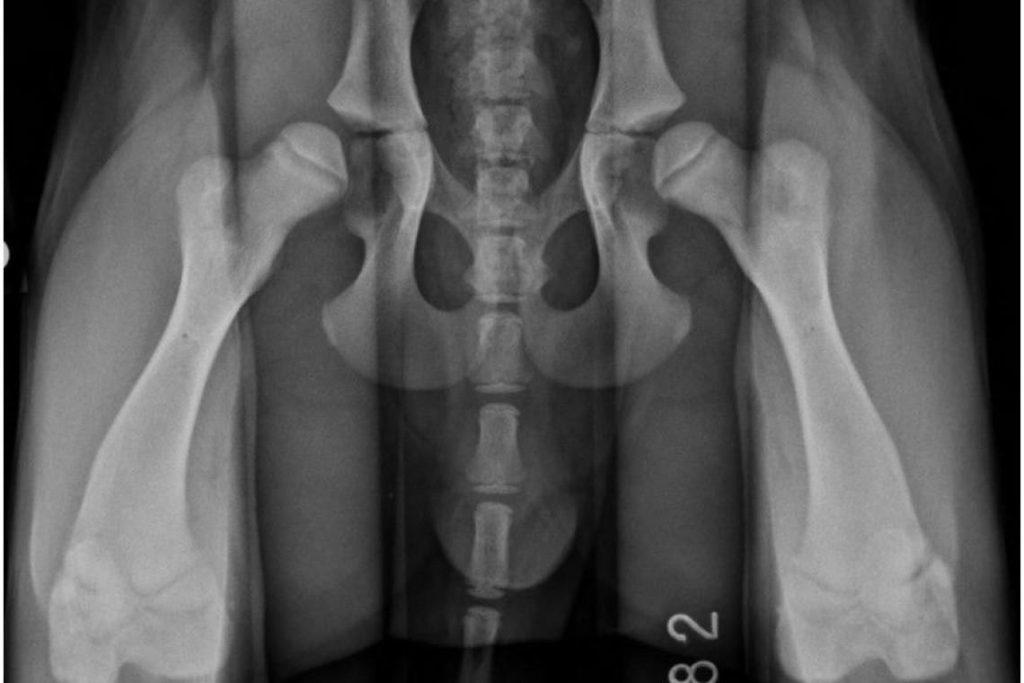

3.狗狗关节发育不良引起

狗狗还很容易又出现髋关节和肘关节发育不良,虽然有点犬种比较不容易遗传那样的疾病,但基本都单独的犬种都能看见了这个症状。那样的发育不良倒致肘关节或髋关节畸形,会让狗狗的坐姿或走路姿势变得很古怪。髋关节和肘关节发育不良,也可疼痛可十分严重。这种疾病,如果又出现症状,一般都在狗狗比较小的时候就能发现自己,可以不通过手术的让狗狗恢复从容自如活动;要是就没做手术干预,这种疾病会剧烈狗狗终生,到后期会会影响狗狗的正常了生活。